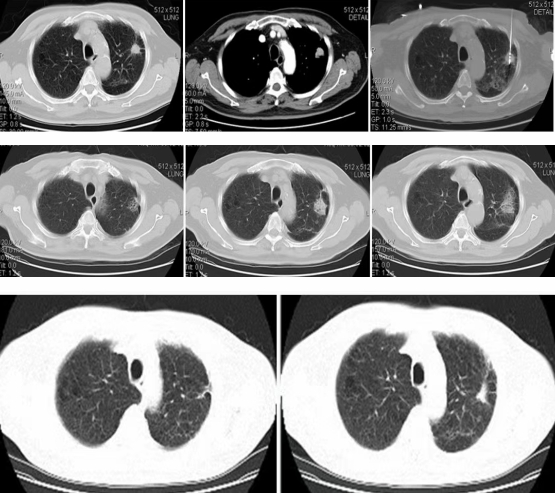

左肺上叶病灶消融术后,病灶缩小呈瘢痕改变